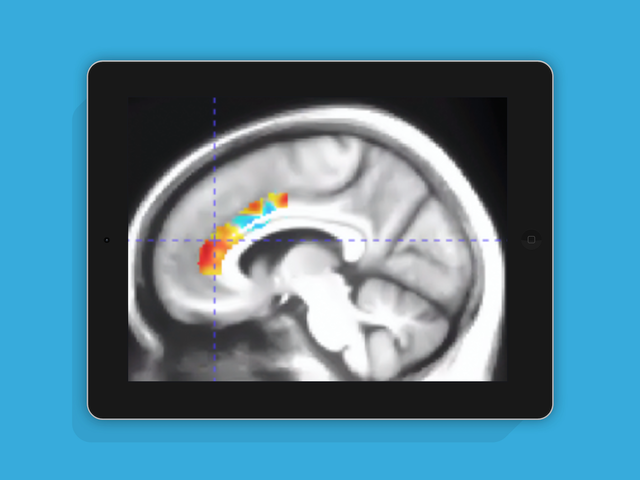

미국립보건원(NIH)의 승인으로 진행된 예비연구, 브레인HQ 게임 6주간 총 12시간 훈련 후 검사

- 아세틸콜린 양이 16~24% 증가

- 전뇌 4개 영역에서 분비- 주의력이 향상되었음을 의미

➡ 아세틸콜린은 주의를 기울일 때 분비되는 신경물질로 학습과 기억에 중추적인 역할을 하며, 노화와 함께 생성이 줄어 치매와 밀접한 관련이 있습니다. 일반적으로 처방되는 치매약은 아세틸콜린 재흡수를 억제하여 치매 진행을 둔화시키는 효과가 있습니다.